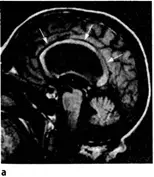

Рис. 2.2.Идиопатическая нормотензивная гидроцефалия.

а. Сагиттальный срез МРТ головного мозга в Τ1-режиме,

Нейровизуализация играет важную роль в диагностике одной из потенциально обратимых форм деменции — нормотензивной гидроцефалии. При этом KT или МРТ головного мозга выявляет преимущественно внутреннюю гидроцефалию, максимально выраженную в области передних рогов боковых желудочков (рис. 2.2).